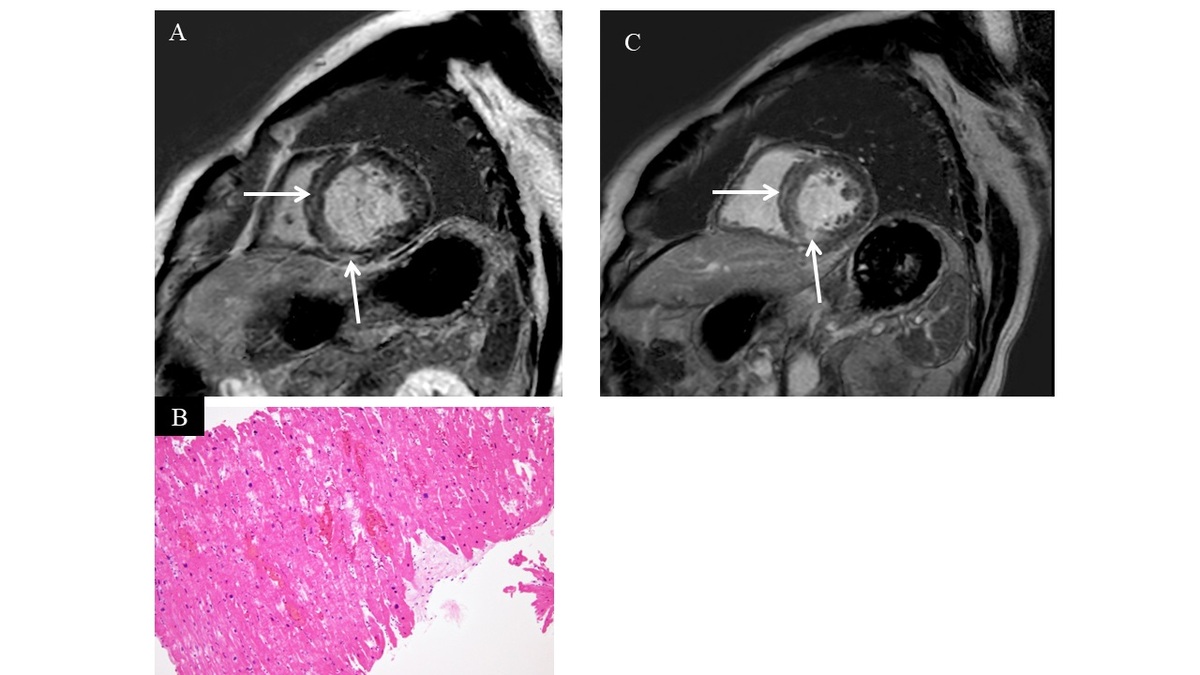

Amano Y, Kitamura M, Takano H, Yanagisawa F, Tachi M, Suzuki Y, et al. Cardiac MR imaging of hypertrophic cardiomyopathy: techniques, findings, and clinical relevance. Magn Reson Med Sci 2018; 17: 120-131.

Amano Y, Aita K, Yamada F, Kitamura M, Kumita S. Distribution and clinical significance of high signal intensity of myocardium on T2-weighted images in 2 phenotypes of hypertrophic cardiomyopathy. J Comput Assist Tomogr 2015; 39: 951-955.

Takeda M, Amano Y, Tachi M, Tani H, Mizuno K, Kumita S. MRI differentiation of cardiomyopathy showing left ventricular hypertrophy and heart failure: differentiation between cardiac amyloidosis, hypertrophic cardiomyopathy, hypertensive heart disease. Jpn J Radiol 2013; 31: 693-700.